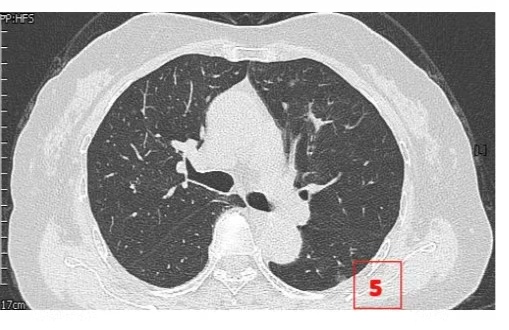

患者女性,71岁,因“发现左肺多发结节2周”入院。胸部CT提示左肺多发磨玻璃结节,较大者位于左肺上叶,呈类圆形,边界清晰,最大直径约9mm。该CT表现高度提示恶性可能。鉴于患者结节数量较多,为减少术中肺组织损伤,术前于CT引导下行经皮肺结节定位术,继而实施胸腔镜下左肺楔形切除术。术中共切除肺部结节6枚。术后病理示:左肺上叶较大结节(4号)为微浸润腺癌,其余5枚结节均为原位癌。患者术后恢复良好,于术后第1天拔除胸腔引流管,第4天顺利出院。

▲术前定位